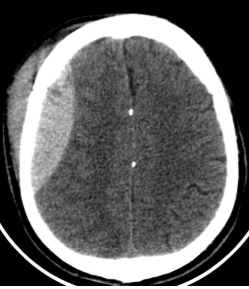

22

What does ventricular effacement look like on CT head, and what conditions does it indicate?

Ventricle looks thinner and smaller, instead of normal wide sickle-shape

Indicates increased intracranial pressure secondary to cerebral odema released from tumour, ischaemic stroke OR haemorrhaging

What is hydrocephalus, and what does it look like on CT head?

Hydrocephalus: Abnormal accumulation of CSF in brain ventricles and spinal cord

CT finding: Ventricles look swollen with loss of sharp points, with dark colour (hypodense due to fluid accumulation)